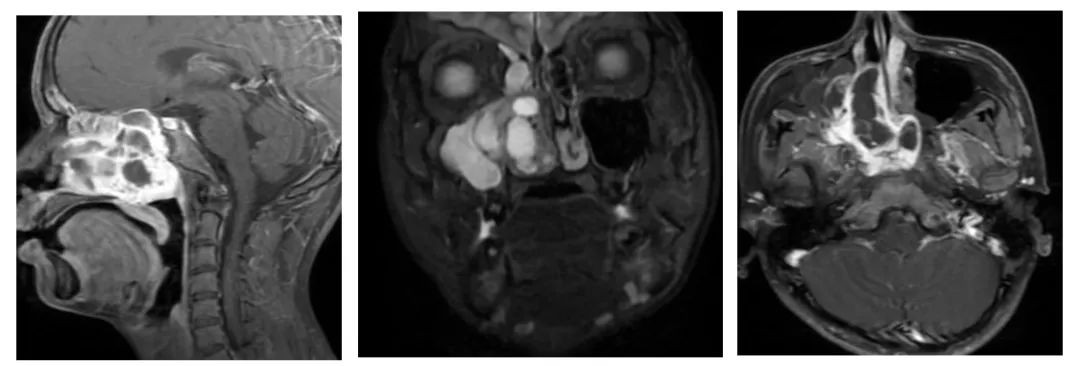

近日,一名16岁的青年因反复鼻出血1年,伴鼻塞、嗅觉下降,严重影响睡眠及学习,便来到了茂名市人民医院耳鼻喉科进行就诊,医院耳鼻喉科副主任吴新权接诊后为小李完善鼻内镜、鼻窦CT及MRT检查,确诊为鼻颅底巨大鼻咽纤维血管瘤。

小李的检查报告提示右侧鼻腔、鼻咽腔、双侧筛窦、蝶窦区见不规则形异常信号影,并且肿物突破鼻腔、鼻窦向周围侵犯翼腭窝、颞下窝、中颅底及眼眶等重要复杂解剖区域,增强CT扫描提示CT值为140,约为正常值的4倍,提示肿瘤的血供丰富,如果不手术治疗会有大出血的风险。为此吴新权主任医师团队组织了由耳鼻喉科、肿瘤科、麻醉科、CT科及磁共振科专家参加的多学科会诊(MDT)。专家们详细研判病情,制定了完善的手术方案,确定了术中、术后各种意外风险的应对预案。